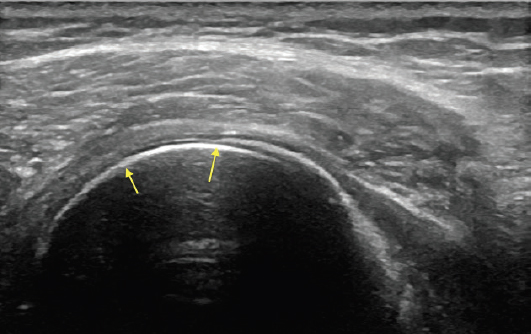

Csont

Az előzőekhez hasonlóan az ultrahang a csontos struktúrákon sem tud áthatolni. A képen kis nyilak jelölik a csont határait, ami mögött a kép sötétté válik, mivel innen nem jut vissza információ az ultrahang fejhez.